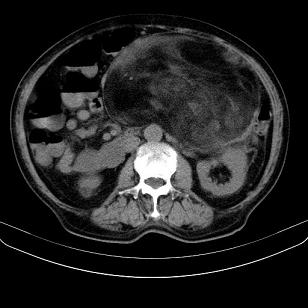

标题: CT21671:男,88岁,左上腹包块 [打印本页]

标题: CT21671:男,88岁,左上腹包块

患者因咳嗽而住院,自觉右上腹包块,无其他不适。

脂肪肉瘤,应测ct值。

支持;后腹膜脂肪肉瘤诊断。

另肠腔扩张及液平,肠梗阻?

考虑腹膜后脂肪肉瘤可能性大。 畸胎瘤不除外。